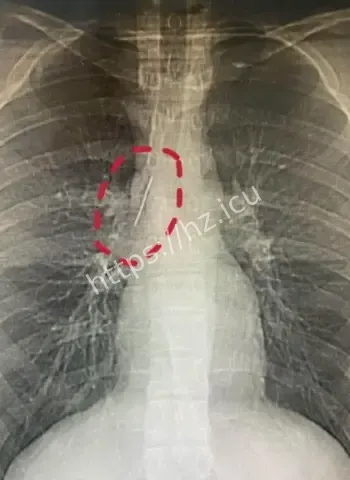

哎呦喂这事儿听起来就跟天方夜谭一样,一个安徽的17岁小伙子平时活蹦乱跳的,准备去参军体检,结果医生一照X光片子,眼睛直接瞪圆了,胸腔里居然稳稳当当藏着一根5厘米长的缝衣针。这针估计从小时候就钻进去了,整整17年啊,小伙子吃饭睡觉打球跑步啥都没耽误,身体愣是没闹过一点别扭。换成别人早疼得满地打滚了,他倒好,像没事人似的,这运气简直逆天到让人羡慕嫉妒恨。 想想这17年里,针就这么安静待着,没移位没发炎没刺着要害,估计是身体自动给它裹了一层保护膜,把它当成了自家摆设。

最离谱的是,这针很可能他1岁那会儿不小心扎进去的。小宝宝那时候到处乱爬乱抓,说不定妈妈正缝衣服,他一扑腾就中招了,结果针就这么悄无声息地进了胸腔。17年过去,他从奶娃娃长成大小伙,针却一直老老实实待着,没引起任何不舒服。平时感冒发烧都没多想过胸口,这适应力也太强了吧。 从道理上讲,小孩子身体正长着,组织慢慢把针包得严严实实,像给它建了个小房子隔离起来。没碰着肺叶心脏血管,纯靠运气加体质,简直是活生生的人体奇迹。

参军体检意外发现胸腔惊人异物

深入扒一扒,这针为啥能跟身体和平共处这么久呢。首先位置挑得好,没扎着要害器官,胸腔空间大给它留了余地。其次人体有自我保护本能,会分泌纤维组织慢慢把它包裹住,防止感染和移位。小时候扎入,身体还在发育,适应起来更容易。再次可能没带细菌进去,运气成分占大头。 这案例搁医学上都算罕见,值得研究研究,说不定以后处理类似异物就有新办法了。不过小伙子以后肯定得做个小手术取出来,不然总是个小隐患。希望手术顺顺利利,他的参军梦还能接着追,这段经历以后说出去绝对是别人听不够的传奇。